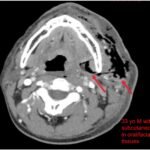

Necrotizing soft tissue infections with mediastinal extension are exceedingly rare. This submission provides dynamic and static visual stimuli (CT images) and a case report describing the history of present illness, initial ED presentation and inpatient course of a 33-year-old man who developed facial necrotizing fasciitis complicated by mediastinitis secondary to odontogenic infection following wisdom tooth extraction. Discussion of the key features of this rare presentation, the diagnostic and therapeutic approaches to making the diagnosis (including CT), and the role of the Emergency Physician, are highlighted.